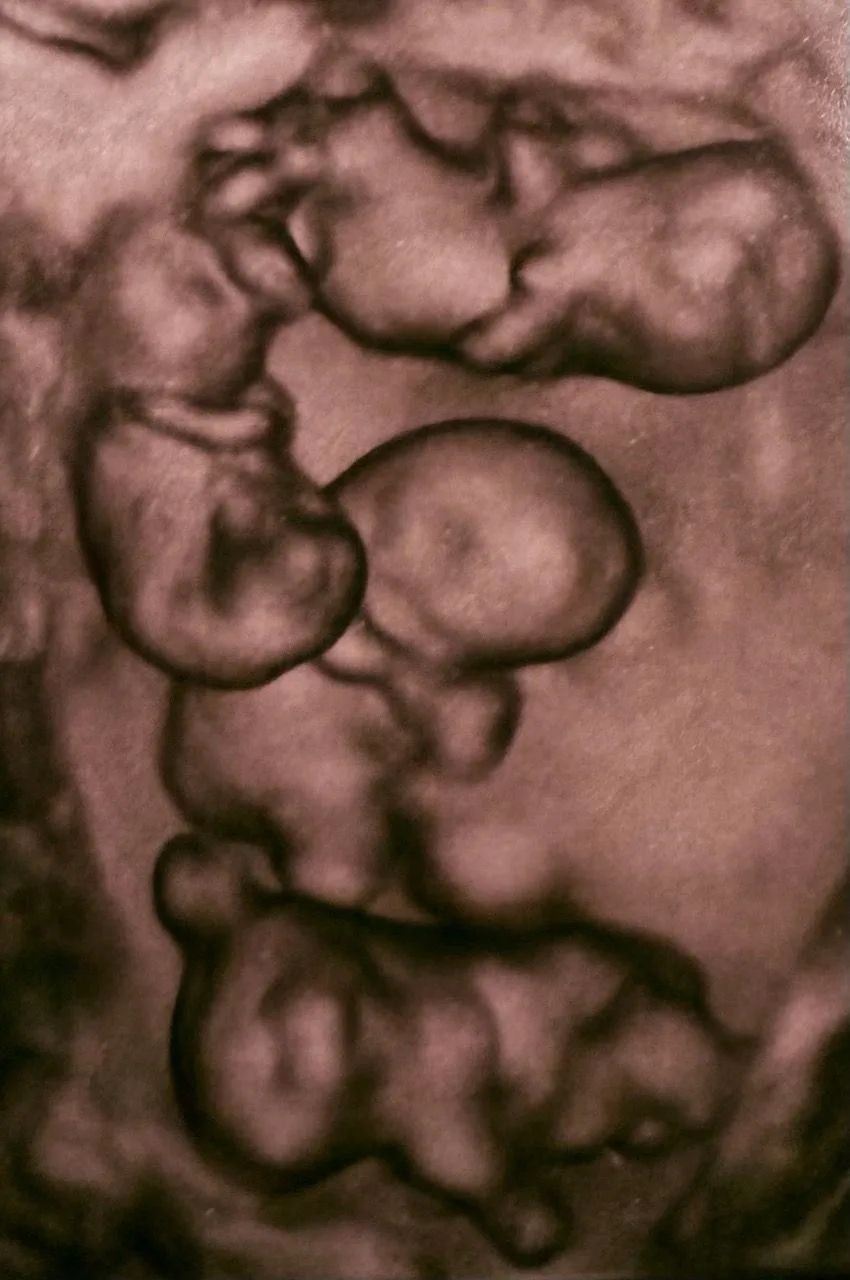

2 апреля в роддоме № 17 в Санкт-Петербурге родилась четверня: на сроке 32 недели на свет появились четыре сестренки.

Об удивительном случае не только в истории медицины, но и России, рассказали в соцсетях роддома.

«В истории нашего родильного дома была написана удивительная и редкая глава. В медицине рождение четверни — это всегда событие экстра-класса, требующее ювелирной точности, колоссальной выдержки и слаженной работы огромной команды. И это чудо произошло!», — поделились в сообщении.